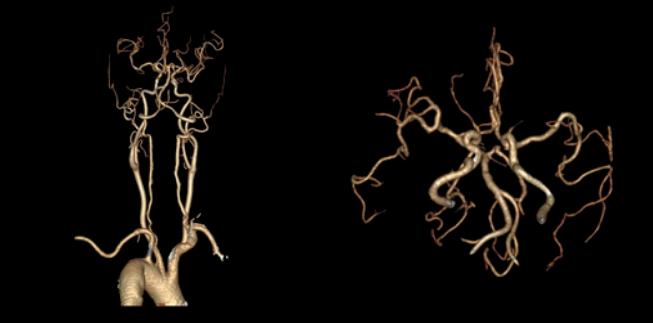

十七、基底动脉延长扩张合并开窗畸形

病例31:基底动脉延长扩张合并基底动脉起始段开窗畸形

病例32:基底动脉扩张延长合并基底动脉近段开窗畸形

病例33:左侧大脑前动脉A1段开窗畸形合并基底动脉延长扩张